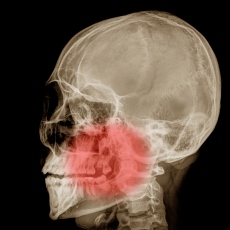

Your jaw is a set of bones that holds your teeth. It includes:

- The maxilla, which is the upper part of your jaw. It holds your top teeth in place and doesn't move. It also supports the muscles involved in chewing and facial expressions.

- The mandible, which is the lower part of your jaw. You move it when you talk or chew. It also holds your lower teeth in place.

- The temporomandibular joints (TMJs), which are two joints (one on each side) that connect your mandible to your skull.

Jaw problems can include:

Diagnostic imaging tests are often used to diagnose jaw injuries and disorders. Your treatment will depend on which jaw problem you have.